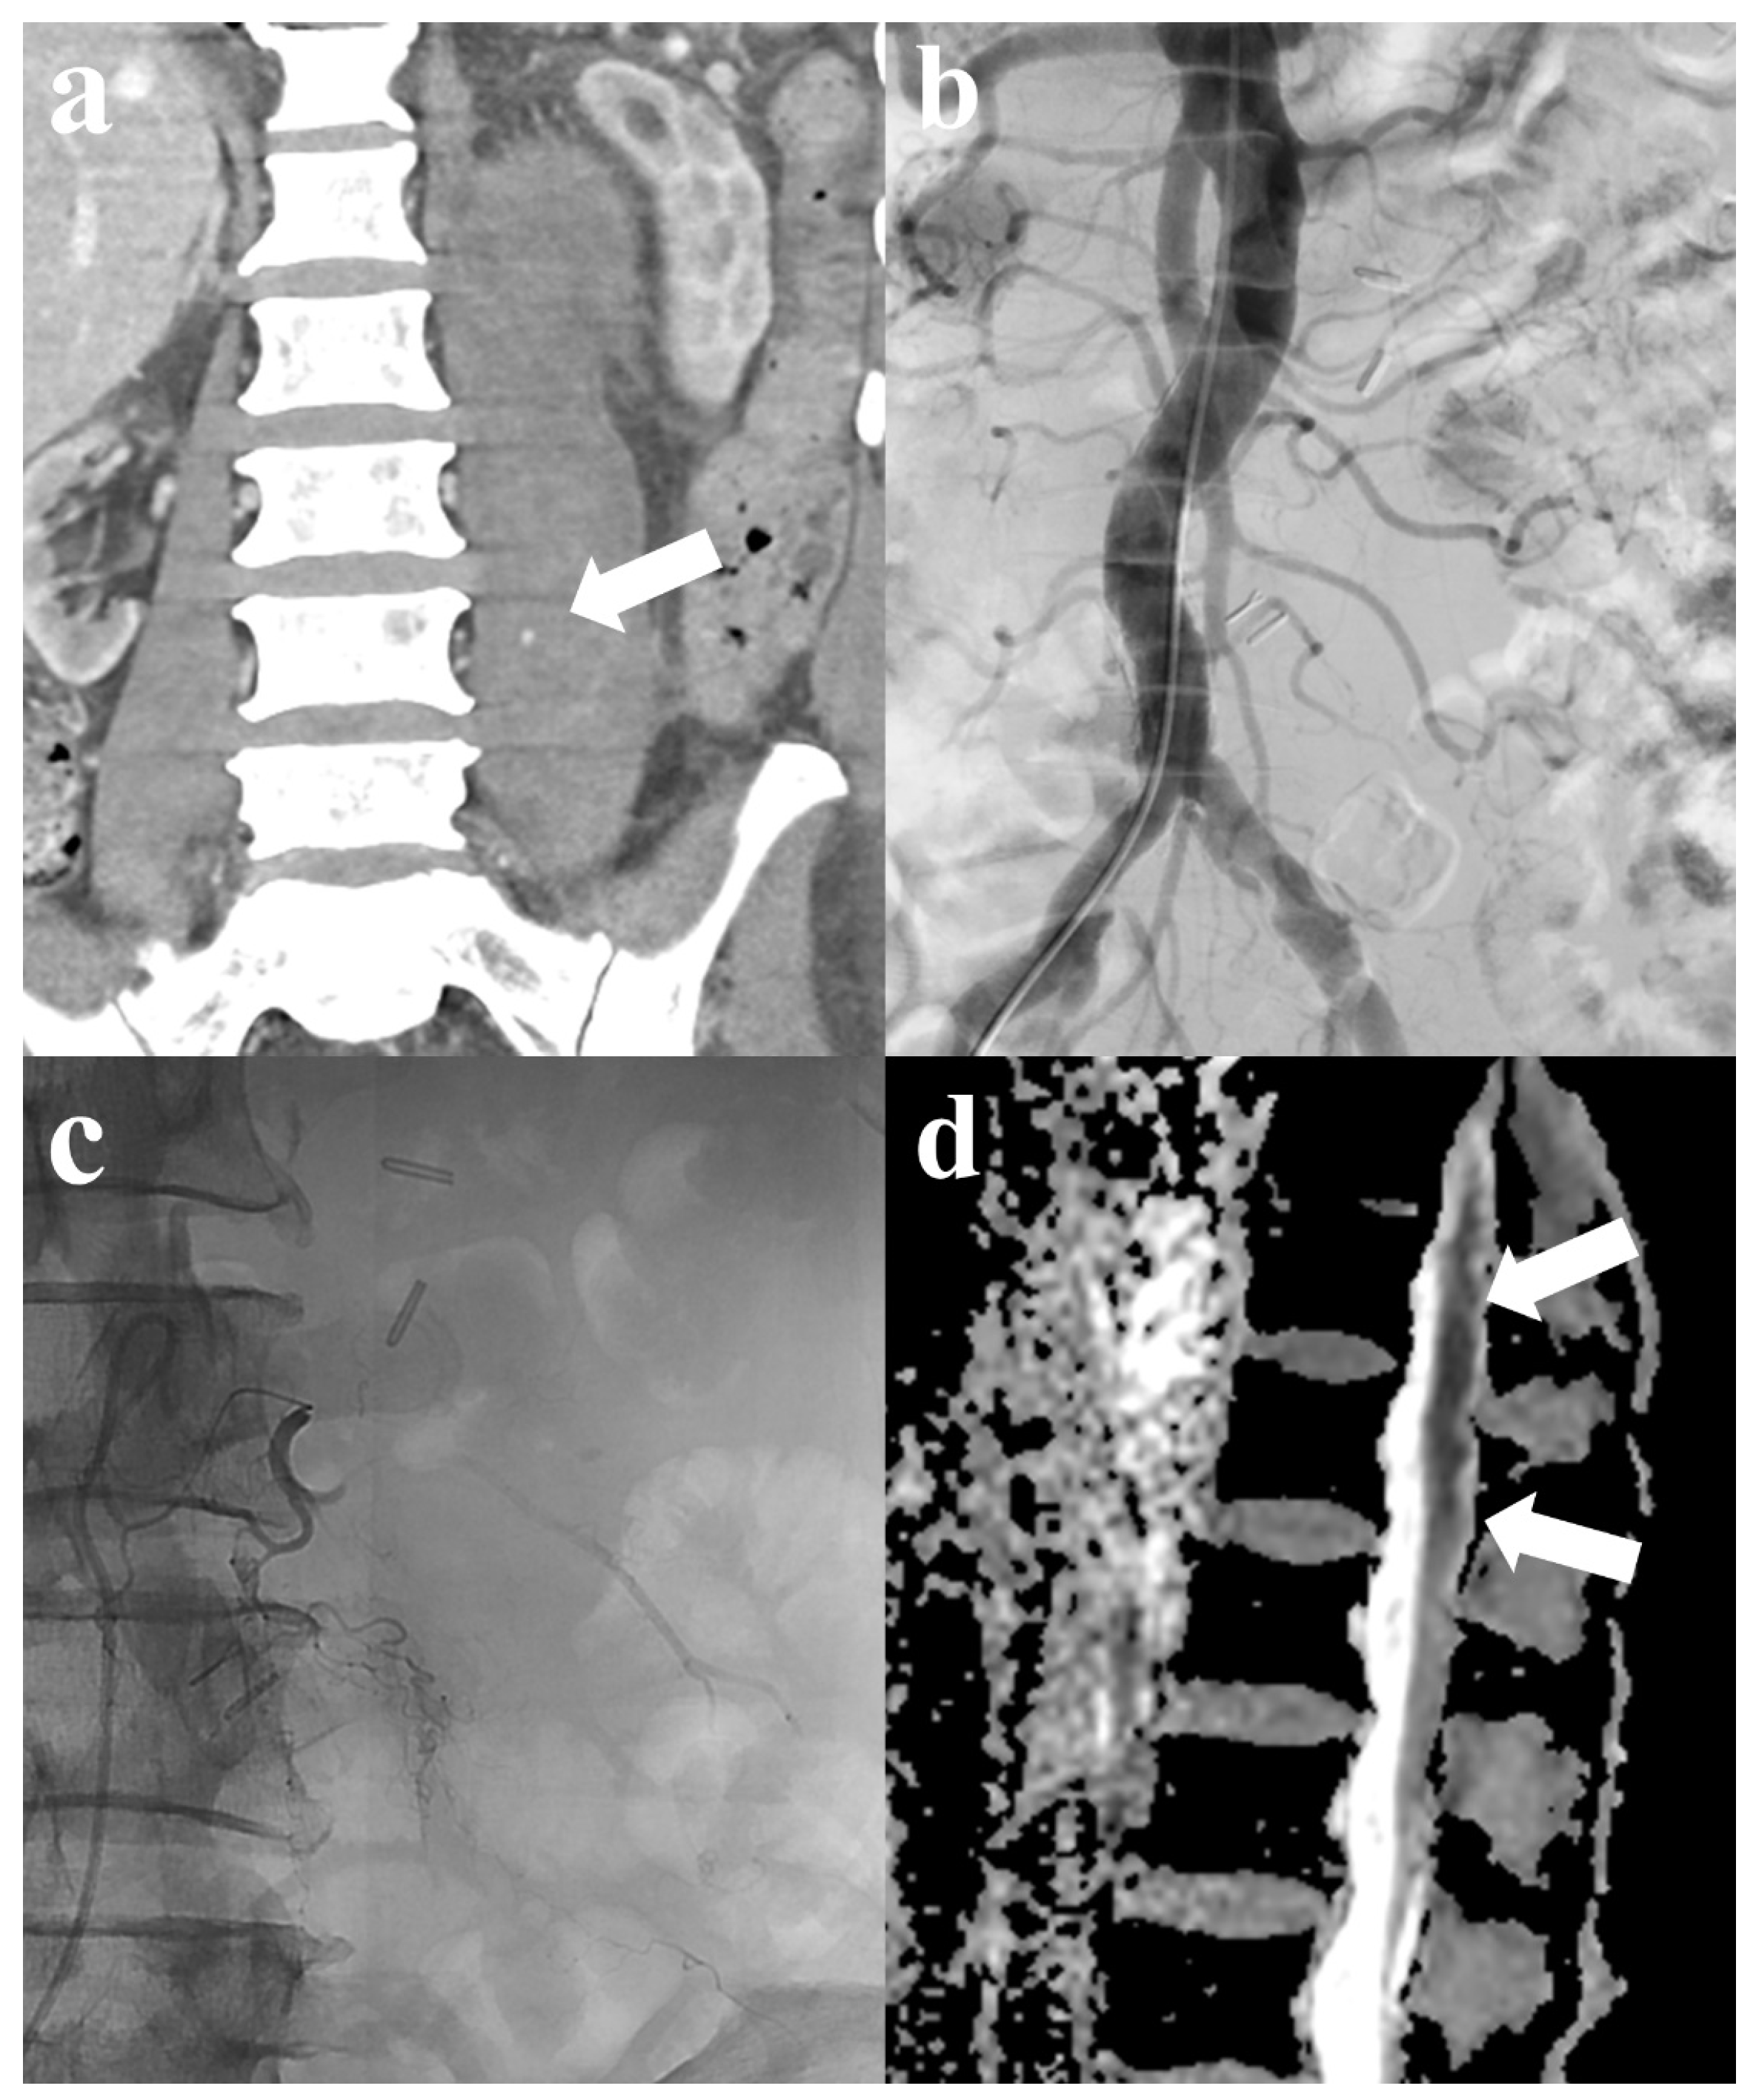

One patient developed motor weakness in the ipsilateral lower extremity after TAE. The patient experienced left spontaneous psoas hemorrhage and underwent TAE. Although active bleeding was not observed on angiography, superselective embolization was performed prophylactically using GSP in the left third and fourth lumbar arteries. However, the patient later developed weakness in the lower limbs on the same side. Subsequent magnetic resonance imaging (MRI) showed diffusion restriction from the lower thoracic spinal cord to the conus medullaris, suggesting spinal cord ischemia (Figure 2). Meanwhile, other patients only developed minor complications, which included mild fever (four patients, 11.1%). These symptoms improved following conservative treatment within 2–3 days postoperatively.

Figure 2.

A 76-year-old male patient with spontaneous psoas hemorrhage. (a) Computed tomography (CT) shows contrast media extravasation with hematoma in the left psoas muscle (arrow). (b) Abdominal aortography reveals no definite active bleeding. Subsequent selective multilevel left lumbar artery angiography also shows no active bleeding. (c) Selective embolization was performed using gelatin sponge particles in the left 3rd and 4th lumbar arteries for prophylactic purposes. (d) After embolization, motor weakness in the ipsilateral lower extremity developed; magnetic resonance imaging (MRI) suggests spinal cord infarction, indicated by suspected diffusion restriction in the lower thoracic spinal cord through the conus medullaris (arrows).